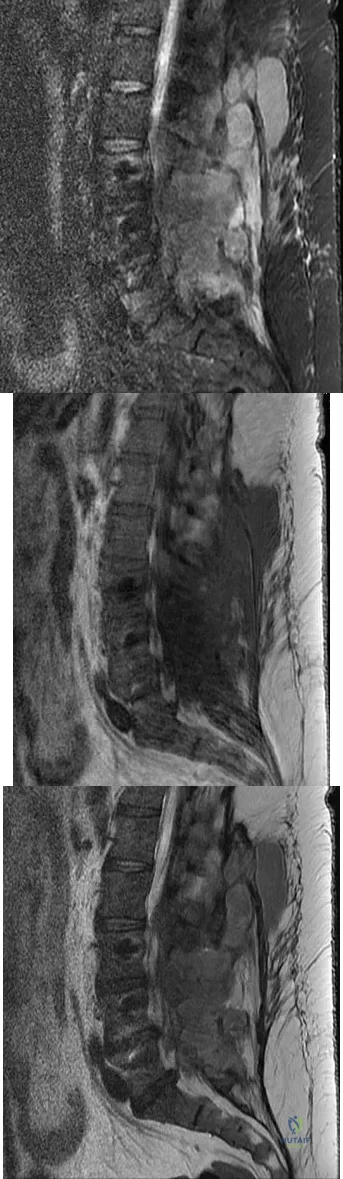

Question 68

A 42-year-old woman underwent an instrumented posterior spinal fusion at L3-S1 with transforaminal lumbar interbody fusion. She had an excellent clinical result with complete resolution of leg pain. Three months later she now reports increasing back pain and weakness in her legs. Examination reveals weakness in the quadriceps and tibialis anterior. Radiographs show no interval changes in the position of the hardware. MRI scans are shown in Figures 2a through 2c. What is the next most appropriate step in management?

Explanation